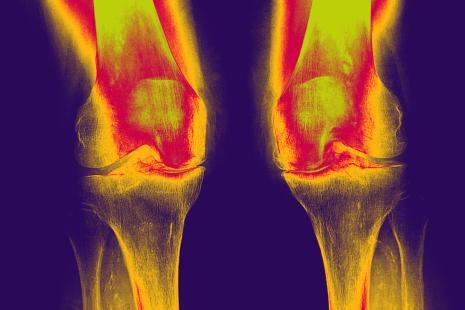

Toutes les composantes de la douleur arthrosique ne sont pas encore comprises. « Cependant, l’arthrose n’est plus considérée comme secondaire à une simple usure mécanique du cartilage, mais comme une affection avec inflammation de bas grade touchant l’ensemble des tissus articulaires », a rappelé la Dr Alice Courties (service de rhumatologie de l’hôpital Saint-Antoine, Paris). Suite à des stress répétés mécaniques ou métaboliques (diabète), se produit une accumulation intra-articulaire de débris cartilagineux qui induit le recrutement de cellules immunitaires, une néo-angiogénèse de la membrane synoviale avec production de médiateurs inflammatoires favorisant la production de métalloprotéases dégradant la matrice cartilagineuse. Un cercle vicieux s’enclenche alors, car de nouveaux débris cartilagineux sont formés.